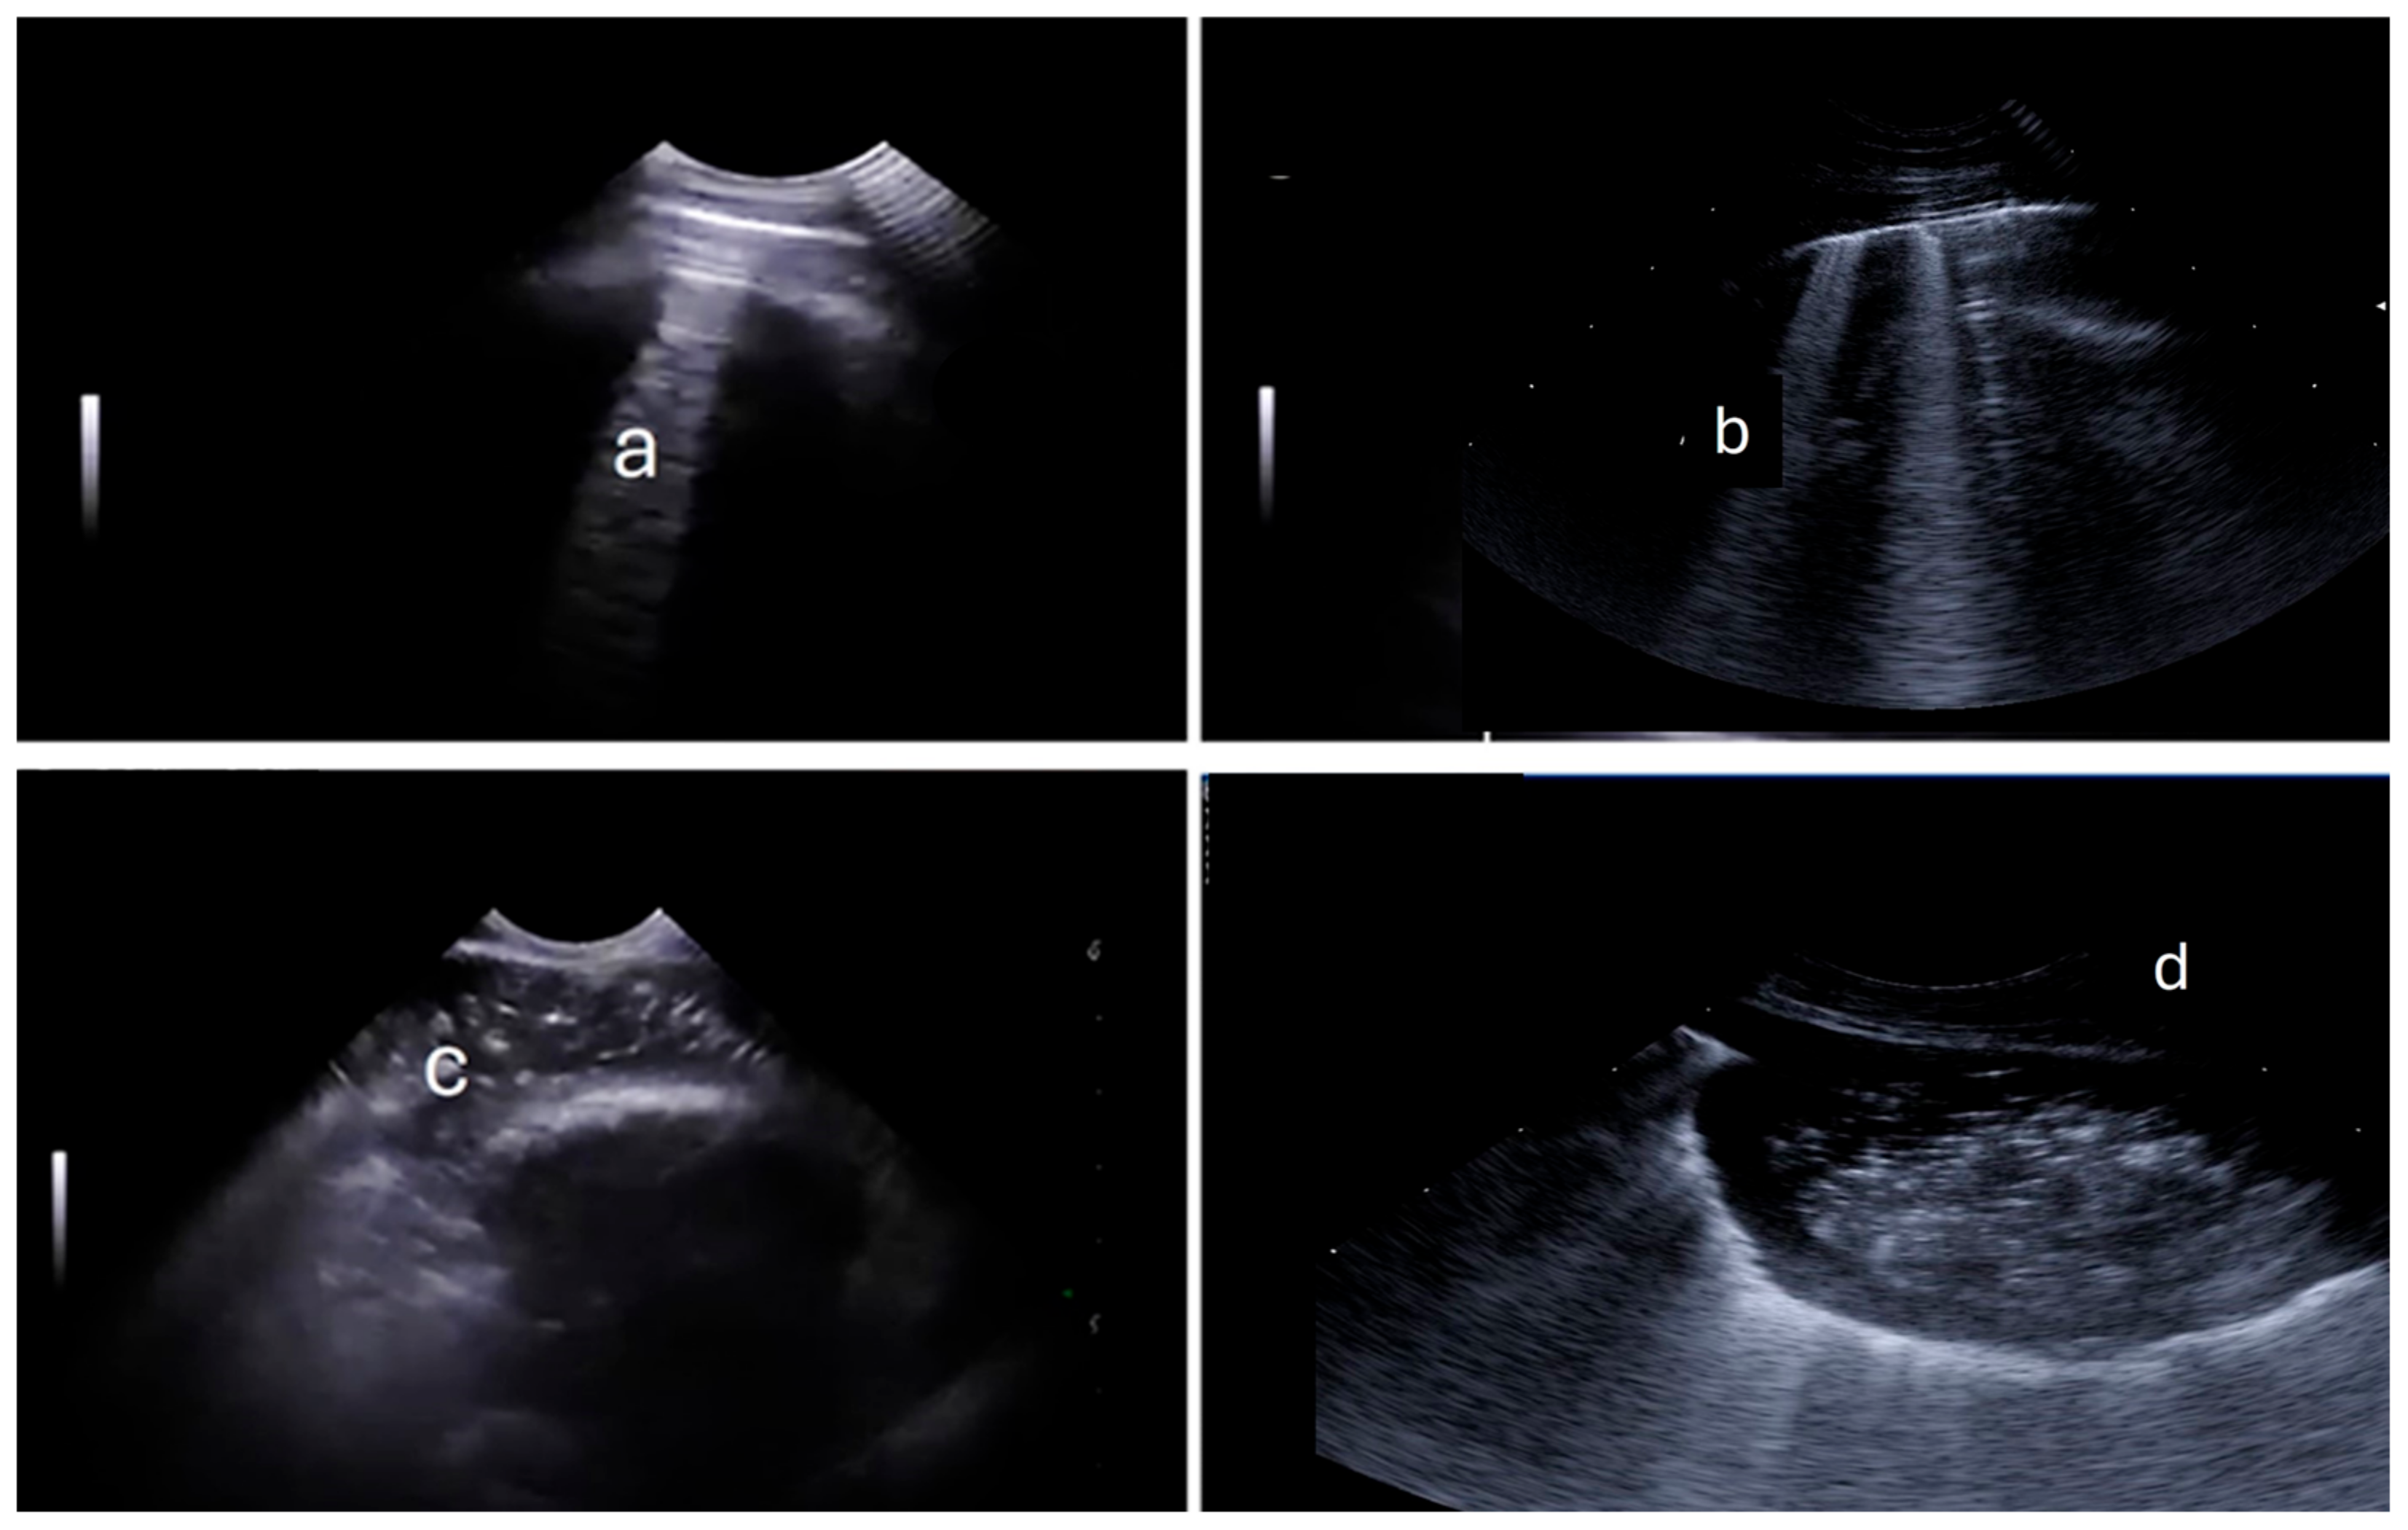

| 1 | Bronquial breath sounds | Sumatory between 3–7 | >5 B-lines, no CON | 10–20% |

| 2 | Crepitations, wheezing and rales | Sumatory between 8–11 | >5 B-lines, <5 CON | 20–30% |

| 3 | Absence of lungs sounds | Sumatory between 12–15 | >5 CON, PF o ABS | >30% |